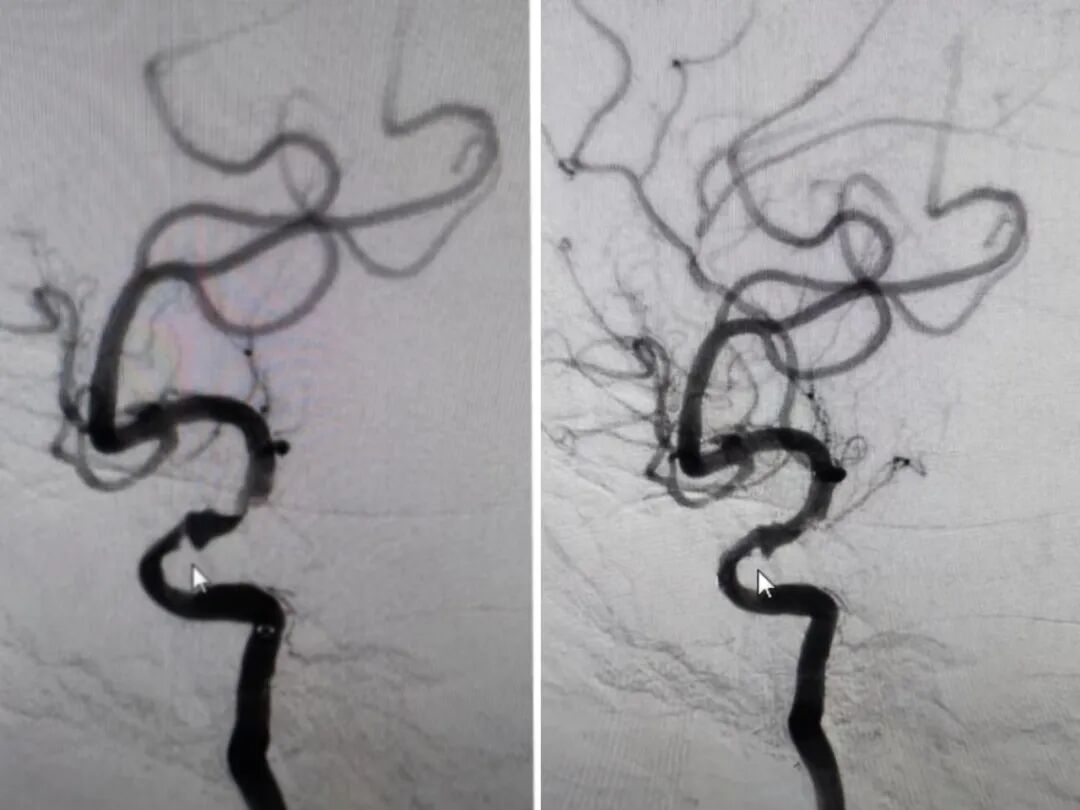

入院后完善检查,全脑血管DSA造影回报:右侧颈内动脉C7段重度狭窄,狭窄程度90%,近端瘤样扩张;右侧大脑前动脉未显影。

↑卒中 中心介入团队为患者颈内动脉支架植入术

术中见右侧颈内动脉C7段重度狭窄,狭窄程度90%,近端瘤样扩张,经导丝准确定位,球囊扩张后将(4.0mm*23mm)支架释放,造影显示支架完全覆盖狭窄段,与血管壁贴壁良好,残余狭窄20%,前向血流(TICI)分级3级,右侧颈内动脉C7近端瘤样扩张 好转;导管回撤到颈内动脉,再次造影提示右侧颈内动脉C7段轻度狭窄,右侧大脑前动脉血流恢复,未见血管痉挛,责任血管供血区域显影良好,手术顺利完成。术后患者恢复良好,表示脑子前所未有的清亮。

右侧 颈内动脉支架植入术前与术后 DS A 对比